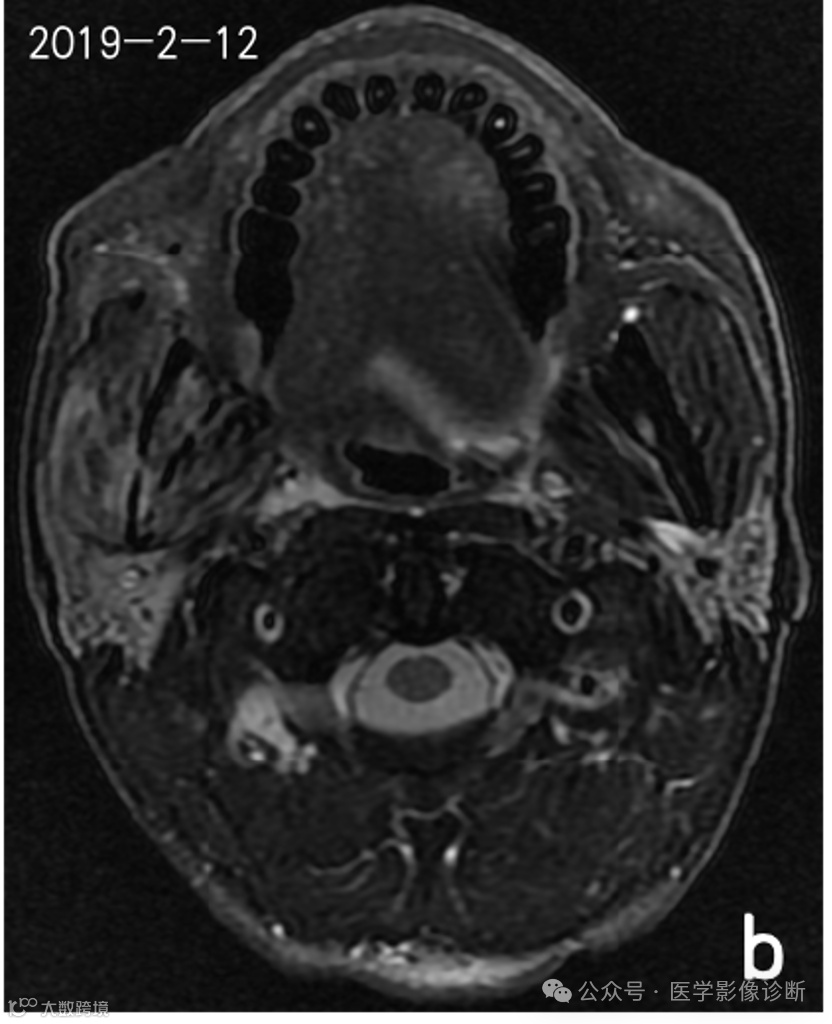

患者,男性,56岁,放疗后患有右口咽癌。

不同时期的四次核磁共振成像显示右下颌骨有异常信号。前两次报告(a、b)均未提及异常信号,说明存在感知错误(漏诊)。在第三次检查(c)中,放射科医生发现了异常信号,但误认为是骨转移,说明存在认知错误(误诊)。患者自2018年以来经常牙龈肿痛的临床查体和治疗情况被遗漏,经过抗炎治疗后,这种症状得到了很大改善。诊断应为右下颌骨骨坏死伴骨髓炎,但放射科医生因不熟悉放疗并发症而导致诊断偏差。